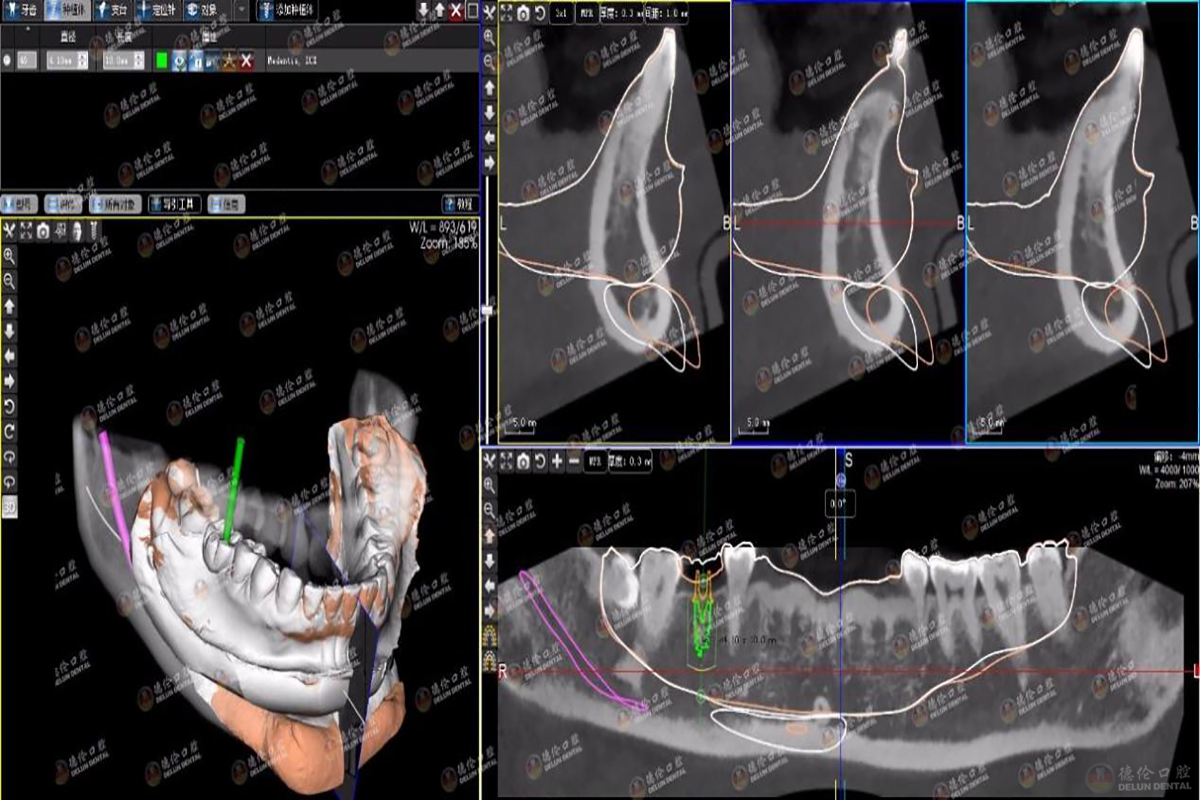

数字化种植牙是利用CBCT和数字化设备进行术前数字化诊断,全面看到患者的口腔信息数据,避开患者血管神经,然后利用3D打印技术,根据患者口腔信息数据,制作出个性化的导板,大大提高手术的准确性,凭借导板的准确定位,之后将种植体植入牙槽内,大大缩短手术时间,实现缺牙者的完美修复。

图为电脑上模拟种牙过程